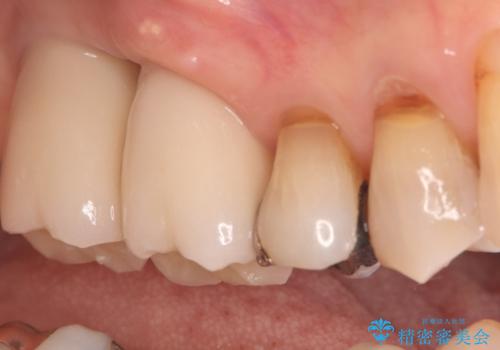

繰り返すプラスチックの欠けを解消。広範囲の修復に適したセラミッククラウン

担当医 河口智英